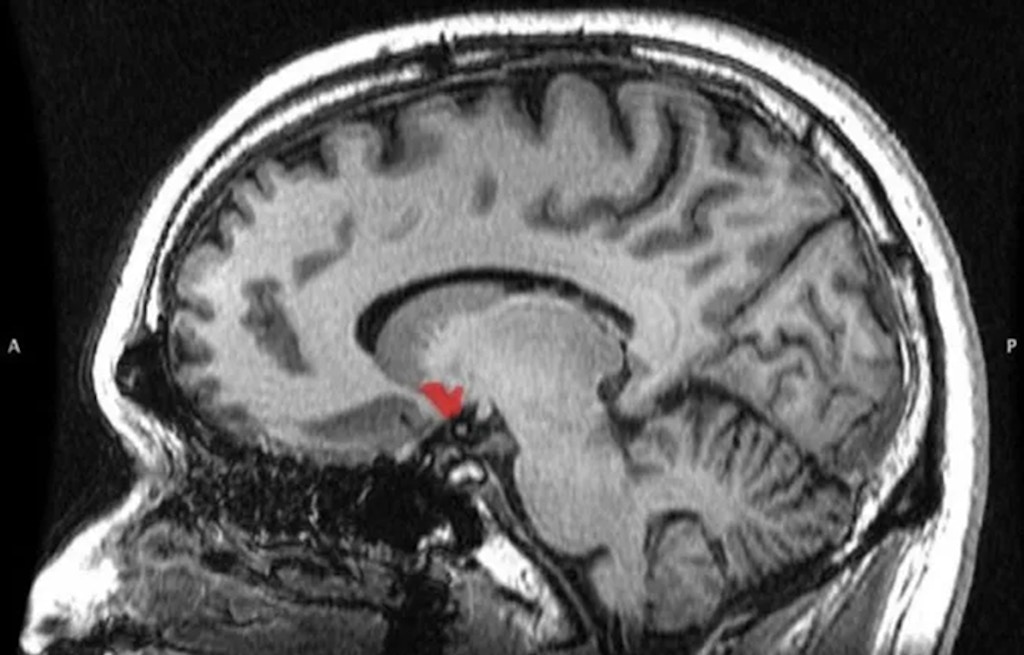

И это неудивительно: образ жизни человека сильно изменился только несколько веков назад, а в масштабах целой эволюции это очень маленький срок —поэтомумозг и не может пока перестроиться. За этот механизм импульсивных покупок отвечают три части нашего мозга: прилежащее ядро, миндалевидное тело и орбитофронтальная кора.

Вот как это работает: когда мы видим что-то классное, вкусное или красивое, включается прилежащее ядро и говорит нам: «А давай купим, потому что нам этого хочется». В этот момент подключается миндалевидное тело и говорит: «Да, очень классно, но, если мы сейчас это купим — нам не хватит на коммуналку, и мы уйдем в долги». После этого орбитофронтальная кора анализирует ситуацию и решает, кто прав — прилежащее ядро или миндалевидное тело, и либо разрешает нам покупку, либо запрещает.

Получается, что в этой схеме роль прилежащего ядра — соблазнить, миндалевидного тела — найти рациональные причины отказа от покупки, а орбитофронтальной коры — вынести «приговор», ориентируясь на то, какое большое удовольствие мы получим сейчас и какая страшная расплата за это ждёт нас потом.